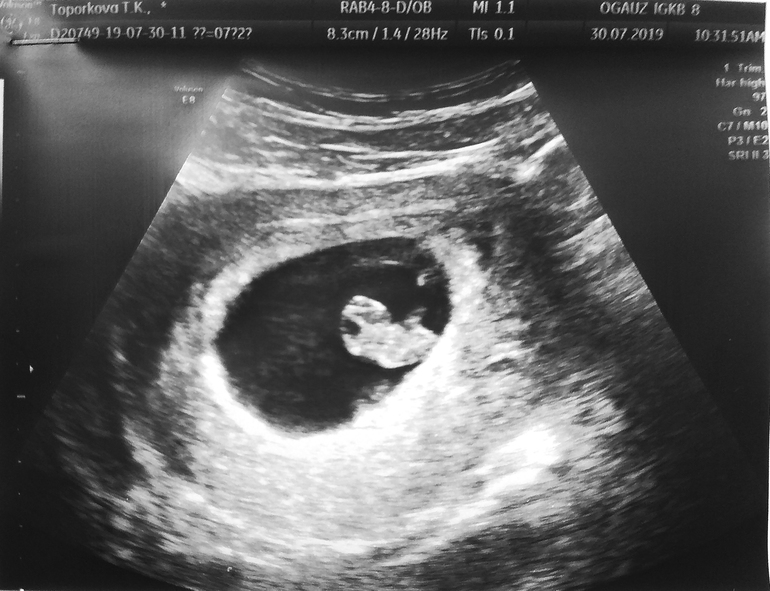

ДругоеВот не разу о таком не слышала. А тут случайно нарвалась на темку и до жути стало любопытно. Девочки кто понимает как это работает подскажите кто у нас. УЗИ было в 7+2 недели смотрели только по животу написано что хорион располагается по задней стенке. Я особо не заморачиваюсь насчет пола и буду рада и дочи и сыночку, но любопытство оно такое)))))

Если я правлено понимаю то поэтому методу у нас вроде девочка получается))))

Доктор Рамзи установил, что в подавляющем большинстве случаев мужского пола плода хорион/будущая плацента располагается в правой стороне матки (97,2%), а в случаях женского пола - в левой (97,5%). Точность метода составляет более 97%, что сравнимо с точностью повсеместно используемых тестов на беременность.

Я полагаю у меня на УЗИ это белый ободок по низу, но это лишь предположения. я сама до конца не понимаю этот метод)))))

Дак на узи все изображение адаптированное и не понять где реально верх, где низ, где право, где лево... 🙈 Они Так-то кверху ногами лежат, а на фотках то "лёжа" на спине, то "стоя", то перелом, то задом... 🤣🤷♀️ Это надо конкретно на узи спрашивать где и как прикрепил ась планета... У меня написано "в дне, с переходом на заднюю стенку", а про лево, право ничего не сказано...

Справа же. Почему девочка? У меня такой вид был но вагинально датчиком. А тогда наоборот. Если по животу то тут мальчик

С дочкой у меня было по передней, а в этот раз по задней. Сама об этом методе только сегодня узнала но так и не поняла как этот метод работает там вроде как важно как смотрели по животу или трансвагинально